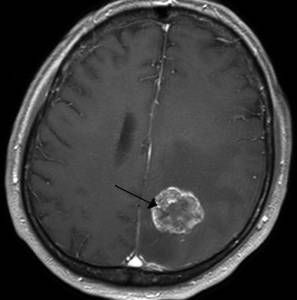

Злокачественная опухоль

Злокачественная опухоль характеризуется появлением патологического новообразования, опасного для человеческой жизни, состоящего из злокачественных раковых клеток, обладающих возможностью быстрого роста и метастазирования.

Тип боли

Интенсивность и характер болевого синдрома зависит от локализации опухоли, тяжести процесса, индивидуальных особенностей организма.

Другие проявления

На начальных стадиях опухоль может никак себя не проявлять вплоть до интенсивного роста новообразования. Тогда самочувствие пациента начинает резко ухудшаться, могут возникать: тошнота, утомляемость, рвота, нарушение слуха и зрения, трудности распознавания речи, расстройства общей и мелкой моторики и т.д.

Клиническая картина при раке очень обширна и многогранная.

Методы диагностики и терапии

Диагностика проводится комплексно и включает: КТ, МРТ, рентгенологическое исследование, лабораторные анализы, гистологию и цитологию. Лечение проводится хирургическое. Пациенту может быть назначен курс химиотерапии или лучевой терапии, а затем длительное медикаментозное поддерживающее лечение.